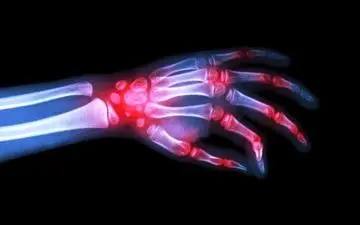

بعد از شکستن قولنج مفاصل زانو، بند انگشت، قوزک پا، کمر و گردن صدایی می شنویم اما آیا میدانید علت این صدای تق تق چیست؟

شکستن قولنج یکی از عادتهایی است که بسیاری افراد برای رهایی از خستگی جسمی انجام می دهند و اغلب خطرات و عوارض جبران…